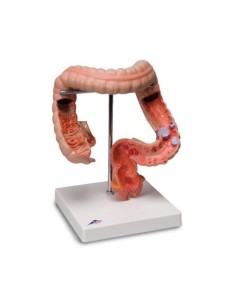

3B Modèle scientifique et anatomique : Pathologies de l'intestin K55

Du crâne en 22 parties à verrouillage magnétique aux modèles de colonne vertébrale, des modèles d'articulation aux modèles de cœur, chaque pièce de notre collection est conçue pour une immersion totale dans l'étude de l'anatomie humaine. Nos modèles, réalisés à partir de scans d'os réels, garantissent une expérience tactile authentique et une fidélité de poids presque identique aux originaux.

Indispensables aux étudiants comme aux professionnels, nos modèles anatomiques sont des outils pédagogiques qui permettent d'observer les structures anatomiques avec précision, en évitant les dissections ou les études invasives. Ils sont également utiles pour expliquer les pathologies aux patients, ce qui rend la communication plus efficace et permet de gagner un temps précieux.